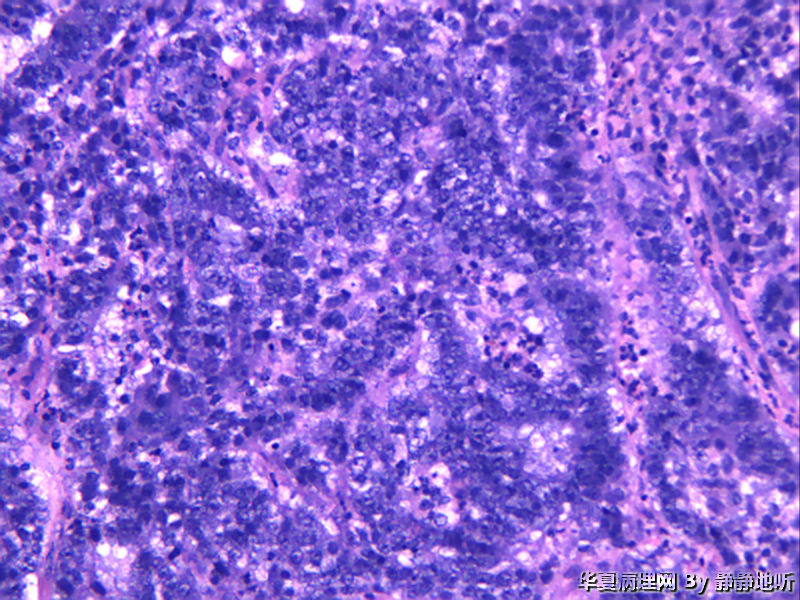

• 子宫肿瘤图1

图1

女性46岁,子宫峡部肿瘤,息肉样,体积3.5*4*3厘米,脱入宫颈,大体侵肌层。子宫肌壁明显增厚,大体似子宫腺肌症。

免疫组化:ck7-    CEA-    ER -   PR -   CD10 -   Vimentin -   ki-67 约60%